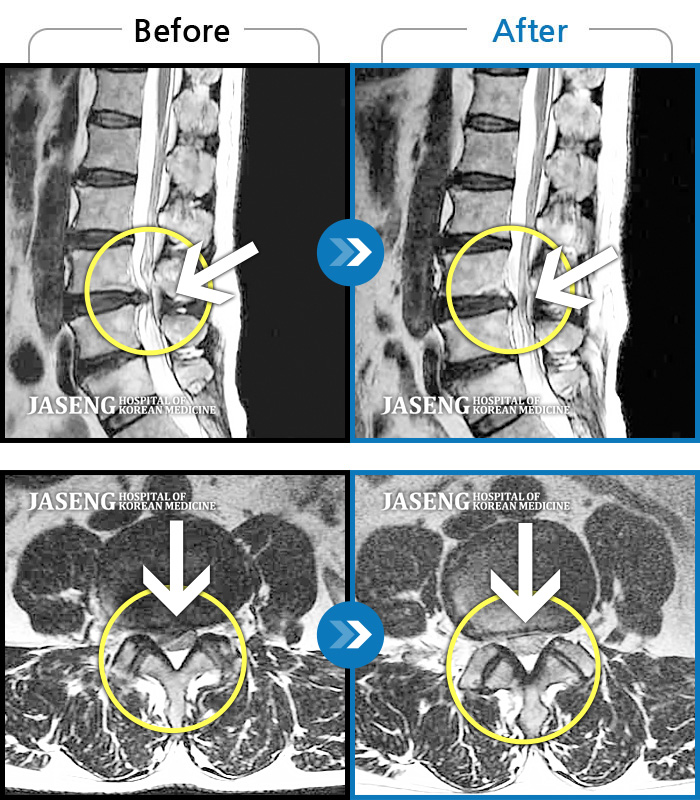

엄청난통증으로 앉지도 서지도 못해 자생에 입원하게되었습니다. 하루하루가 괴로워 밥도 제대로 못먹고 진통제맞아야 살만했습니다. 평범한 일상생활하기까지 꽤 오래걸릴거라 예상했는데 자생에서 박정우쌤께 침맞고 물리치료 도수치료받고 일주일도 안되어 회복되었습니다. 디스크가 두개나 터졌는데 한방병원에서 치료가되겠냐고 수술을하던지 해야지 빨리 양방병원으로 옮기라고 답답하게 보시던 주변분들이 저를보고 자생으로 와야겠다고하시네요. ㅎㅎ 흔들리지않고 자생을 믿은보람이 있습니다. 박정우쌤~ 주치의 김영경쌤 ~치료 잘해주셔서 너무 감사하고 감사합니다. 침 잘놔주셔서 저 안아프고 잘움직여요. 아이들에게 금방 갈수있게 해주셔서 감사해요. 쌤들 말씀 명심해서 척추관리 잘하겠습니다. 항상 건강하시고 저처럼 아픈환자들 훌륭하신 침술로 고통속에서 구원해주세요~~